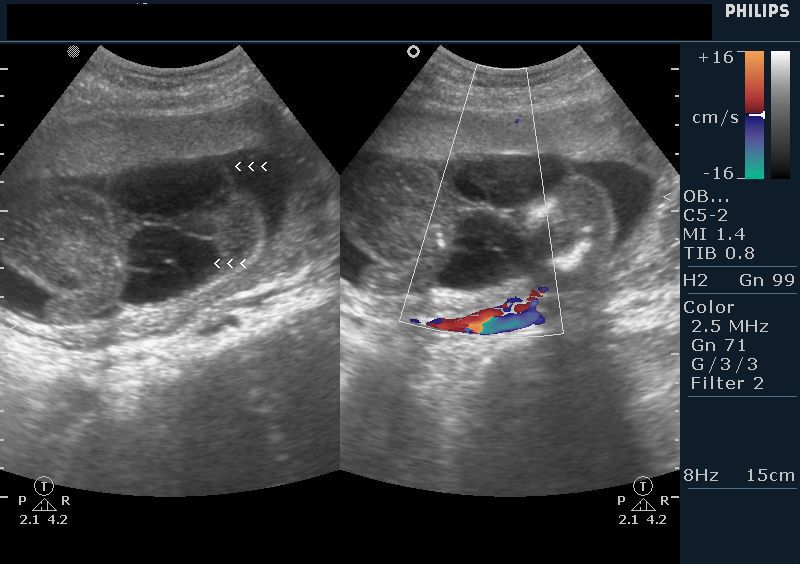

Cystic hygroma

The above ultrasound images show a 16 week fetus with a septate cystic mass in the posterior and lateral aspect of the fetal neck. Color Doppler image shows that this mass is not the cord or part of it. The cystic tumor is almost 7 x 4 cms. in size. The fetal head shows evidence of mild scalp edema (early fetal hydrops). The fetal spine and calvarium show no bony defects, thus ruling out the possibility of fetal meningocele or myelo-meningocele, encephalocele etc. This ultrasound picture is a typical appearance of cystic hygroma. The ultrasound findings of large size of the cyst, septae and posterior location suggest poor prognosis for this fetus. Images are courtesy of Dr. Vikas Shukla, MD, India.